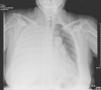

Presentamos el caso de una mujer de 59 años con historia de hidrocefalia normotensiva que requirió DVPT para su tratamiento. Ocho años más tarde la paciente es sometida a cirugía abdominal por diverticulitis aguda perforada. La evolución posterior es tórpida, con episodios de meningitis de repetición y fistula de LCR a nivel nasal. Ante dichas complicaciones y la cirugía abdominal previa, se decide la colocación de DVPL programable. Al cabo de unos meses la paciente ingresa en la UCI por insuficiencia respiratoria de instauración progresiva hasta hacerse de reposo, con criterios de gravedad. A la auscultación presenta disminución del murmullo vesicular en el hemitórax derecho, y en la radiografía de tórax se observa un derrame pleural derecho masivo (fig. 1). Se practica toracocentesis evacuadora e inserción de tubo de drenaje intratorácico. El líquido presentaba características bioquímicas compatibles con hidrotórax. Tras incrementar la presión de apertura de la válvula y la evacuación del derrame, la evolución posterior fue satisfactoria.